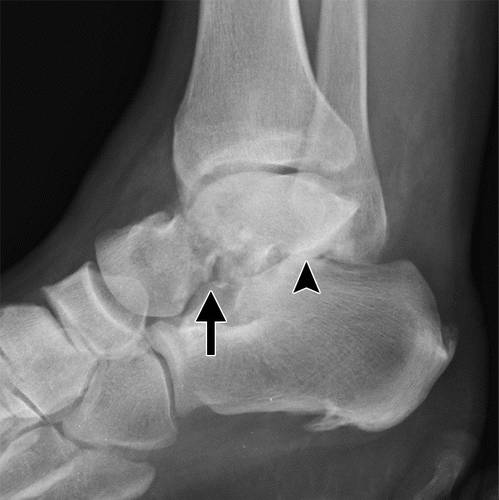

这种损伤必须与三角骨 - 一个附件后骨小梁区分开来。 在放射照相术中,后过程的断裂显示不规则的边缘(图13),而三角骨是圆形或椭圆形,具有光滑的皮质边缘(图14)。 双侧X线照片的价值有限,因为据报道三分之二的病例是双侧的(32)。 如果射线照片不确定,应进行CT。

图13b后突骨折。 (a)右足的外侧X光片显示在距骨后方的小骨质碎片(箭头)。 (b)右脚的轴向CT图像显示后路过程骨折(箭头)以及粉碎的程度和程度。